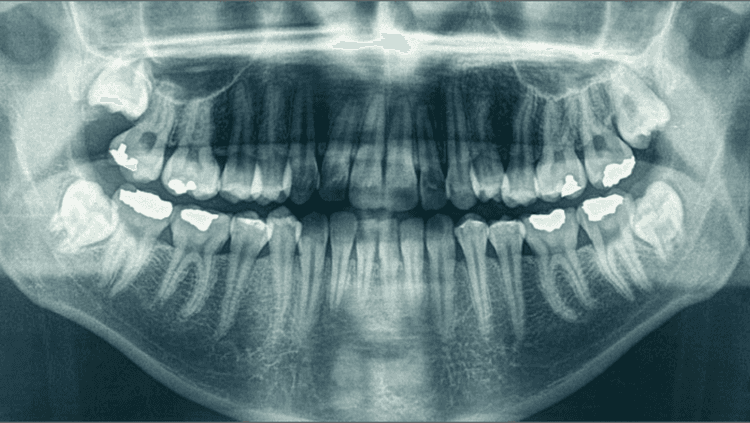

अशा दाताचा एक्स रे करून घेणे आवश्यक असते.

एक्स रे मध्ये जर कीड फक्त दाताच्या कडक भागात असेल तर अजूनही फक्त दातात सिमेंट भरून हा प्रश्न सुटतो.